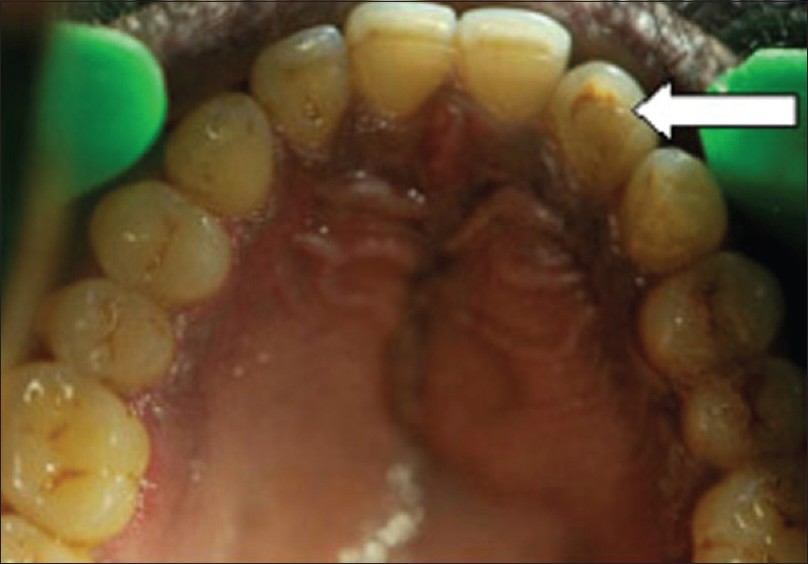

Giant calculus |

p. 174 |

Treville Pereira, Subraj Shetty, Svylvy Pereira DOI:10.4103/2278-9626.134857 |